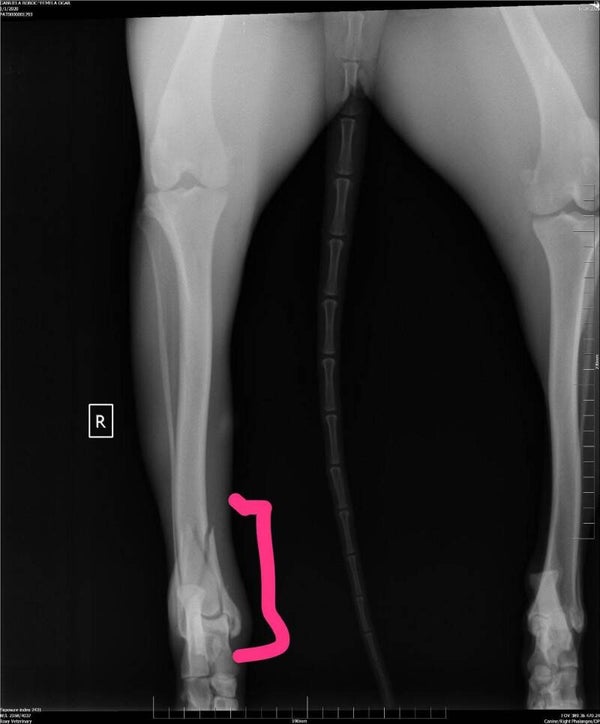

Histoire : Draissy a été jetée à la rue et mordu par des chiens errants à plusieurs endroits. Sa patte arrière était cassée, elle a été opérée et ça va de mieux en mieux. Gabriela l'avait ramené chez son propriétaire mais comme sa patte était cassée, il est venue l'abandonner chez Gabriela le lendemain... Draissy a besoin de connaître une vraie vie de famille et caresse l'espoir d'être adoptée !